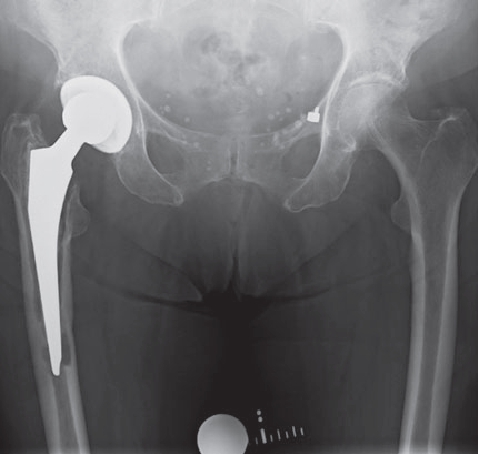

In order to diagnose these infections, tissue samples are taken from the joint in addition to a puncture, as only close cooperation between orthopedists, pathologists and microbiologists can ensure the correct diagnosis. In addition, we also devote ourselves to obviously infected prostheses, of course. These infections can occur shortly after the operation (so-called early infection up to 6 weeks postoperatively) but also years after the operation (as so-called late infection). In addition to the smallest entry points (e.g. an ulcerated toenail), serious infections such as pneumonia can also lead to bacteria colonizing the surface of the prosthesis. Patients with a limited immune system (e.g. diabetics, rheumatics) are particularly at risk. If an infection is noticed early enough after surgery, it is occasionally still possible to eliminate the infection without removing the prosthesis by carefully cleaning the wound and changing the moving parts.

However, infections often go unnoticed for many weeks, so that removal of the prosthesis is unavoidable. Depending on the pathogen and its sensitivity, a placeholder containing antibiotics is then implanted, which remains in place for 6 weeks. Antibiotics in tablet form must then also be taken for this period. However, it is not necessary for a patient to remain in the hospital during this entire period. If home care is not possible, for example, it is also possible to organize this in close cooperation with our social services. After 6 weeks it is generally possible to reimplant a prosthesis, provided that the blood values show that the infection is under control. Antibiotics must then be taken again for 6 weeks after surgery. Which antibiotics are taken is determined in close cooperation with colleagues in microbiology and clinical pharmacology, with whom regular rounds and therapy checks are carried out. These therapeutic measures are carried out in a special area of the clinic using the most modern methods.

Infizierte HüfttotalendoprotheseKniegelenkinfektion nach EndoprotheseImplantierte Spacer nach ProthesenentfernungVorgefertigte Spacer (Platzhalter) mit Antibiotika